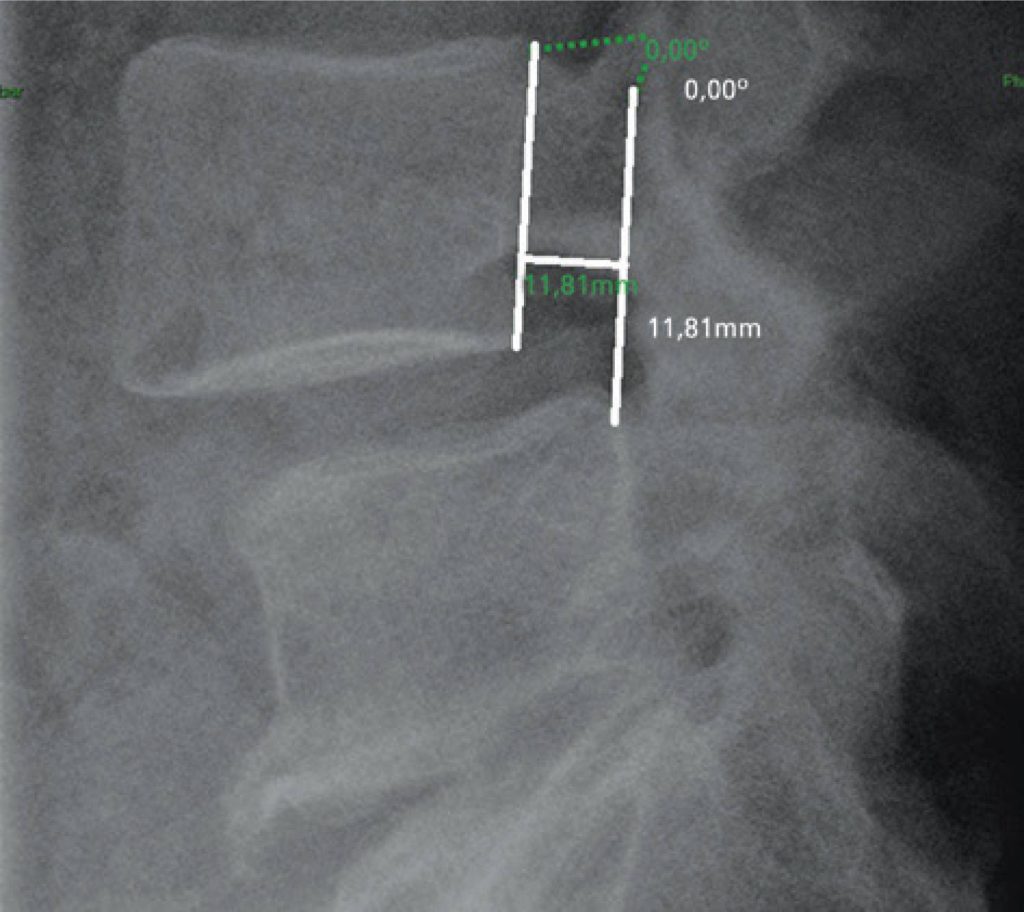

Foram realizadas mensurações das radiografias dinâmicas de coluna lombar na incidência em perfil, avaliando-se a translação anterior e a angulação entre os corpos vertebrais. Os exames foram avaliados em workstations da própria instituição, por meio do sistema Vue RIS (PACS) da Carestream Health, versão 11.0.12.14 Inc. 2009©.